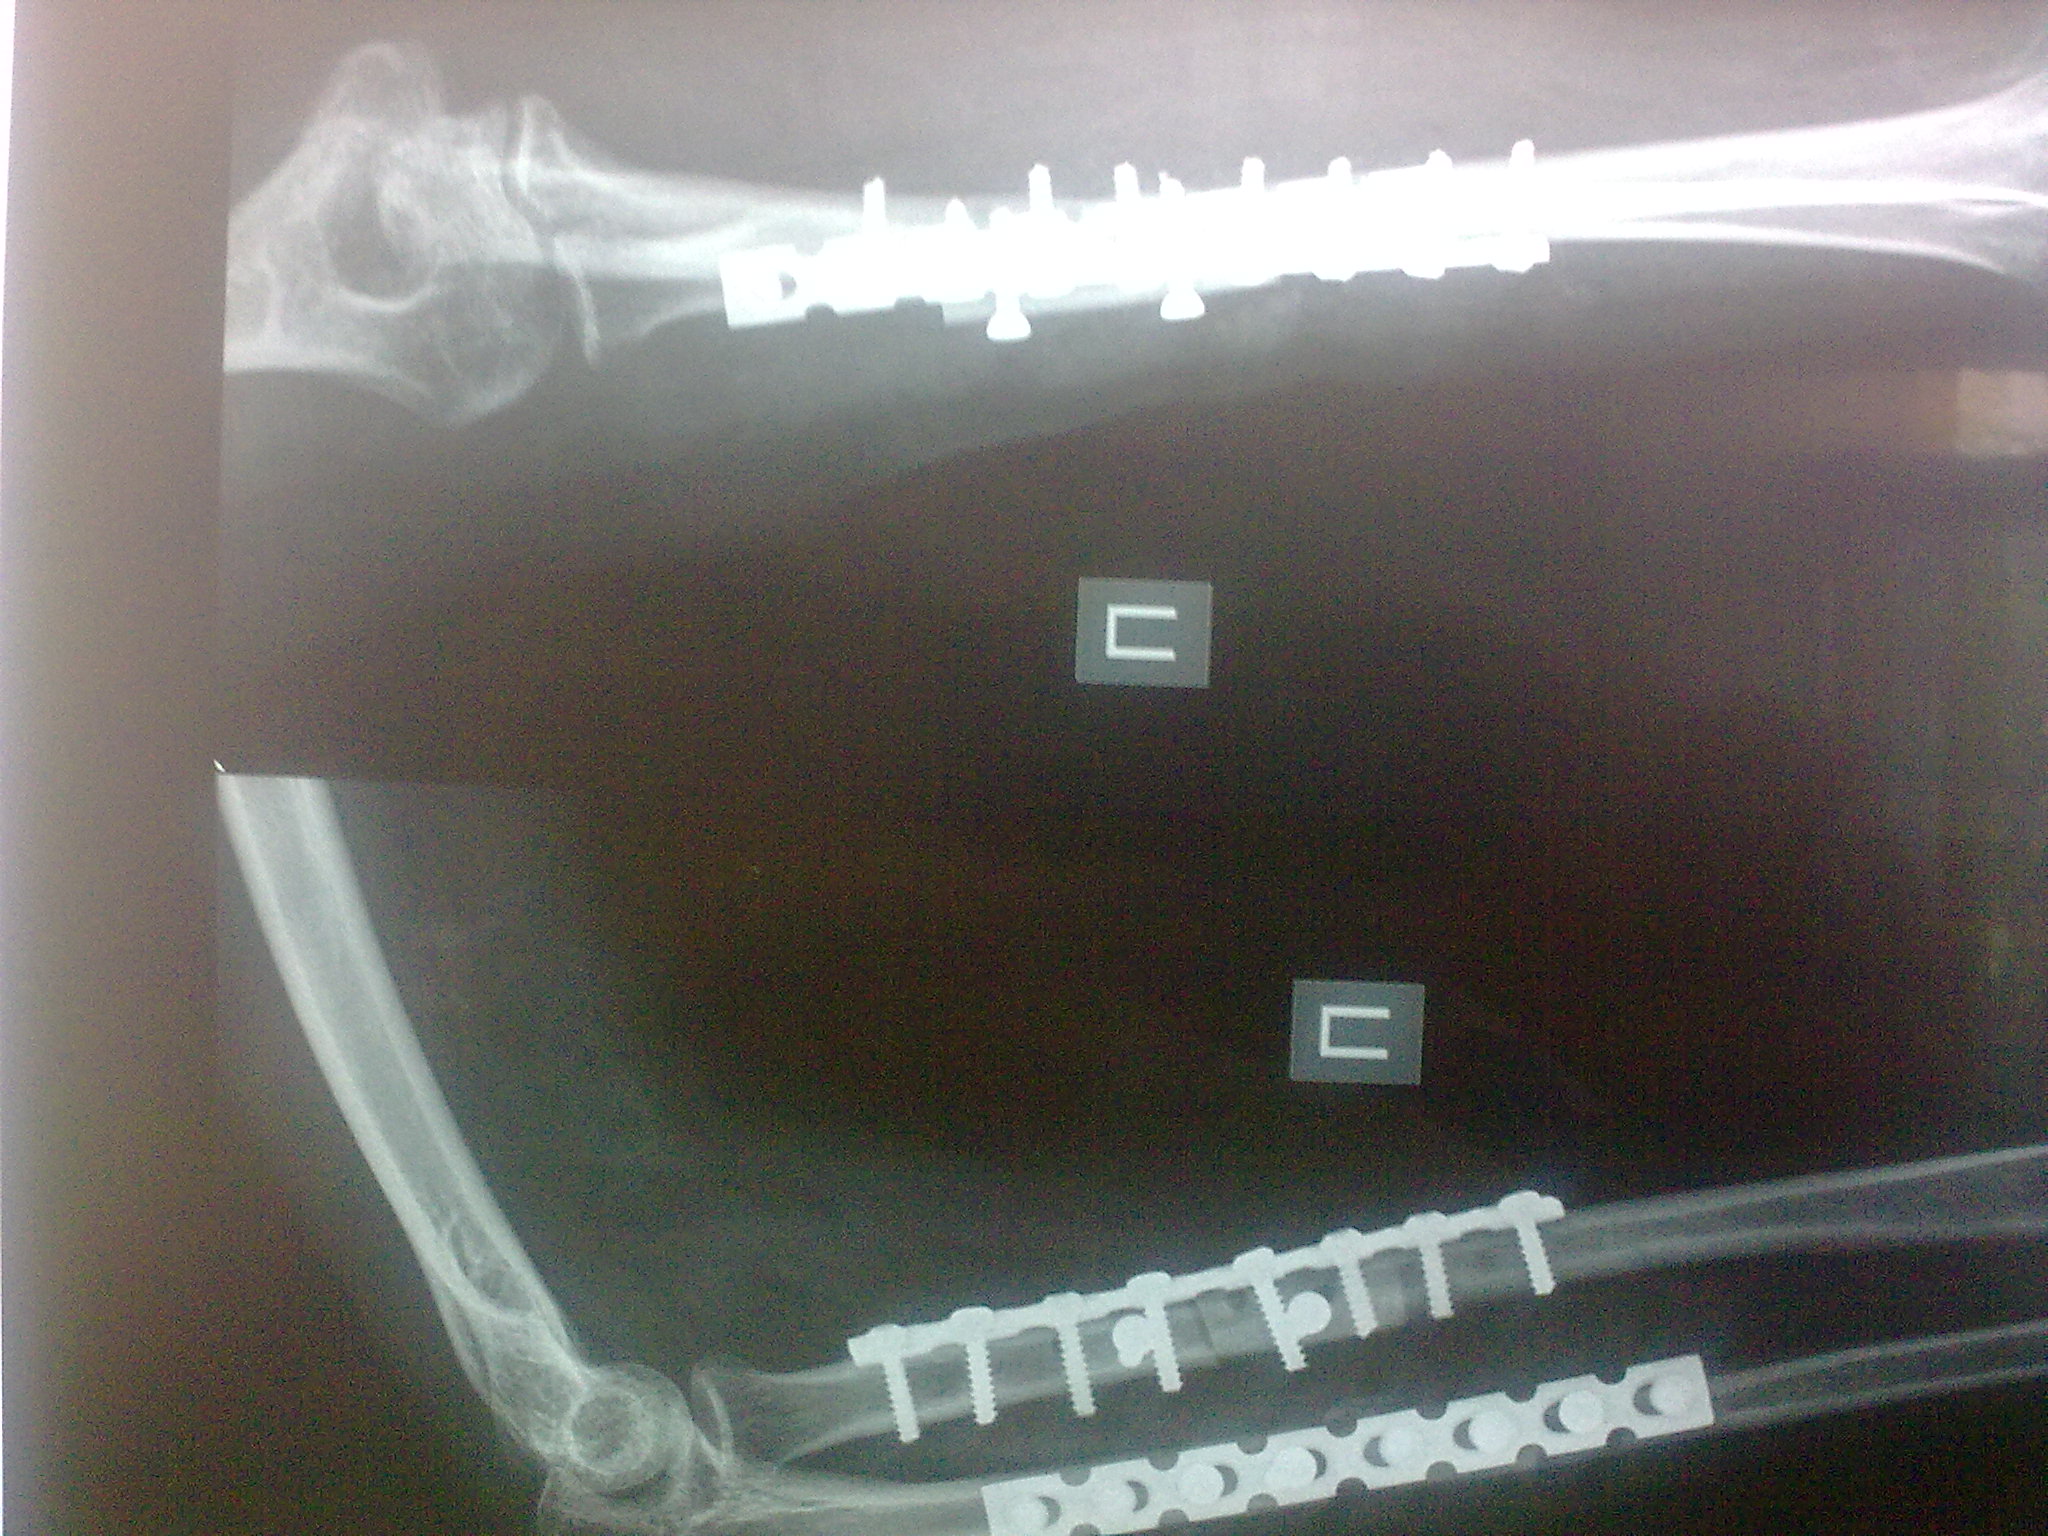

Пациентка С. 23 лет. В марте 2009 года операция остеосинтез костей предплечья пластинами по поводу оскольчатого перелома.

04.07.09. при совершении супинационных движений предплечья ощутила хруст (низкоэнергетическая травма). На рентгенограммах несросшийся перелом костей предплечья, перелом конструкций. Коллеги подскажите что делать, поделитесь опытом.

Спасибо коллеги. Выполнили ресинтез реконструкционными пластинами с костной аутопластикой кортикальными трансплантатами с декортикацией.

Кликните для загрузки файла 16072009402[1]